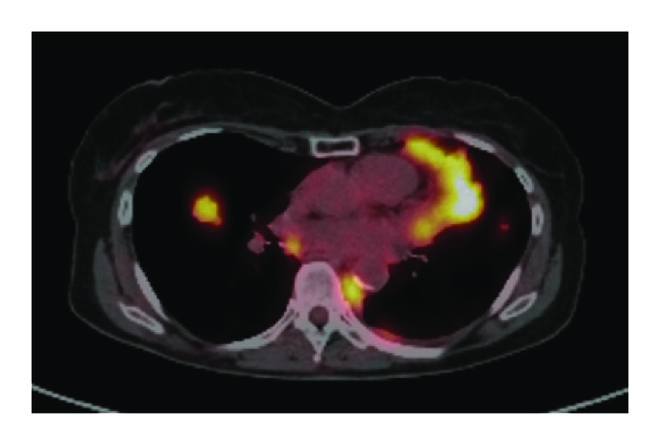

(a)

(b)

(c)

For the 108 patients included in this study, we found 195 instances of disease progression on ET that prompted a change in therapy. Progression was characterized as follows: diffuse progression, progression in greater than 3 sites; oligoprogression, progression in fewer than 3 sites with prior diffuse metastases (>6 sites of disease); and oligometastatic disease with progression, progression in 3 or fewer sites with prior limited metastases (<6 sites of disease). Examination of the patterns of failure revealed diffuse progression in 150 courses (77%), oligoprogression in 28 courses (14%), and oligometastases with progression in 18 courses (9%). On a per patient basis, most patients (69%) displayed only diffuse disease progression, with a smaller percentage of patients displaying oligoprogression (21%) or oligometastases with progression (10%) at least once in their disease course. Though these patients with oligoprogression or oligometastases with progression were similar in age and prior treatment to those patients who progressed diffusely, the patients who progressed diffusely were more likely to be Her2− (84% versus 74%, ), have more than 6 sites of disease at metastatic diagnosis (80% versus 56%, ), and have boney metastases (72% versus 47%, ) (Table 3). Additionally, though the median time to progression with each course of ET appeared similar between the two groups (Table 2), the overall survival of the patients that displayed diffuse progression was significantly shorter than the patients with oligoprogression or oligometastases with progression (median survival 3.1 years versus 6.5 years, ) (Figure 1(b)).

Of the 23 patients with oligoprogressive disease, 11 patients had only one site of progressive disease, 10 patients had two sites of progressive disease, and 2 patients had three sites of progressive disease. The most common sites of oligoprogression were bone (), liver (), locoregional (), and lung () (Figure 2). In addition, mixed locoregional and boney metastases were noted in two patients and one patient developed brain metastasis. Unfortunately, given the limited number patients in this study, no treatment or demographic factors were identified that were specifically associated with oligoprogression.